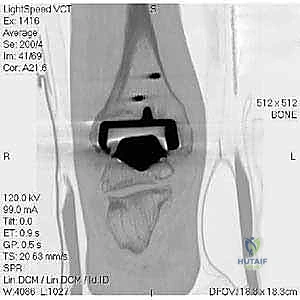

- Computed Tomography (CT) Scan: Extremely valuable for evaluating the presence and healing of malleolar fractures.

- Preoperative Planning: In delayed cases, CT is indispensable for visualizing the fracture pattern, quantifying bone loss, and planning screw or plate placement. Subtraction software can minimize artifact from the prosthesis.

- Monitoring Healing: Crucial for quantifying union before discontinuing immobilization.